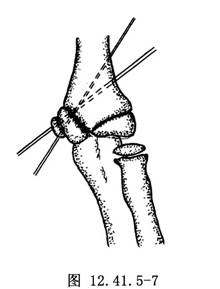

若骨折后无移位可非手术治疗,屈肘位石膏托固定6~8周。若骨折有明显移位者可行肱骨内髁骨折切开复位术手术治疗。